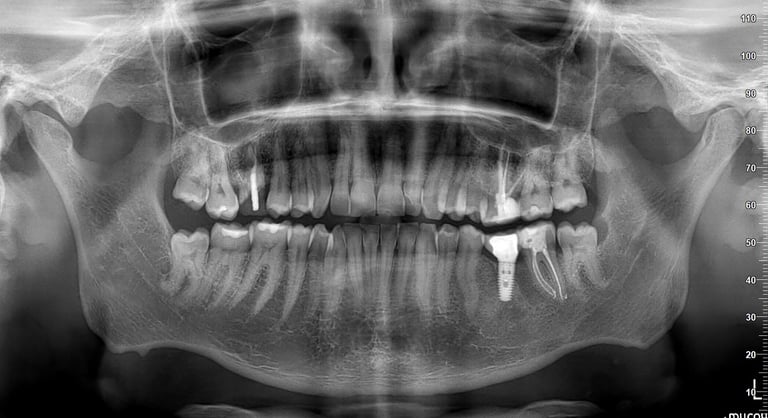

Ортопантомографията или т. нар. Панорамна снимка (зъбни снимки или снимки на зъби) показва общ изглед на съзъбието, челюстите, максиларните синуси и темпоромандибуларните стави. Изследването е стандарт в ежедневна практика на денталния лекар при сваляне на зъбния статус и прилежащите твърди тъкани, за контрол преди и след проведено дентално лечение. Чрез нея се откриват вродени аномалии, патологични процеси, фрактури, кисти и положението им спрямо костта, състоянието на алвеоларния гребен, съотношението между синусния контур и апексите на зъбите, използва се за визуализация на зъбни зародиши при ортодонтско лечение и др.